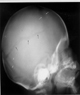

Fractura de cráneo

En este caso podemos observar con líneas blancas dos fracturas verticales de cráneo y con negras una fractura horizontal.